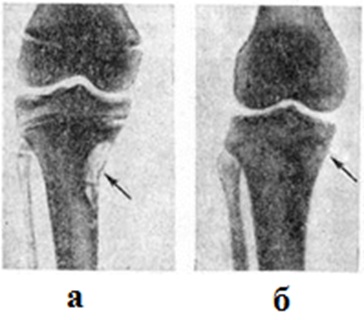

Рис. 6.

Рентгенограмма нижней трети голени и голеностопного сустава мальчика 11 лет с фиброзным кортикальным дефектом в метадиафизе большеберцовой кости в прямой (а) и боковой (б) проекциях. Дефект (указан стрелкой) имеет ячеистую структуру.

Информация об Ordo Deus Перейти в оглавление сайта

Рис. 7.

Прямые рентгенограммы костей верхней трети голеней и коленных суставов больной с фиброзным кортикальным дефектом: а — субпериостальный дефект с ячеистой структурой в метафизе большеберцовой кости (указан стрелкой); б — рентгенограмма той же больной через 2 года; дефект заполнился плотной костной тканью, корковый слой восстановился (указан стрелкой).

Фиброзный кортикальный дефект появляется в постнатальном периоде и бывает связан с повышенной статикофункциональной нагрузкой на определённый сегмент кости. Развитие фиброзных кортикальных дефектов характерно для детей со статико-функциональными нарушениями опорно-двигательного аппарата (сколиоз, плоскостопие, варусная и вальгусная деформация коленных и тазобедренных суставов и другие). Фиброзный кортикальный дефект проявляется развитием локальной зоны дегенеративно-дистрофической перестройки обычно в метафизарных отделах длинных трубчатых костей, у мест прикрепления связок и сухожилий. Очаг может быть одиночным, но нередко очаги возникают одновременно или последовательно в нескольких костях (например, на медиальной поверхности дистального метафиза бедра и медиально-задней поверхности большеберцовой кости). Возможно развитие фиброзных кортикальных дефектов в костях разных конечностей. Значительно реже очаги выявляются в субпериостальных отделах седалищной кости, лопатки и ключицы. Микроскопически очаг поражения представлен пучками коллагеновых волокон и вытянутых клеток фибробластического типа, среди которых можно встретить многоядерные гигантские формы.

Для клинические, картины фиброзного кортикального дефекта характерно медленное нарастание локальных болей и ограниченная припухлость мягких тканей. Нередко патологический процесс протекает бессимптомно, а очаги поражения обнаруживают случайно, при проведении рентгенологическое исследований по другому поводу.

Рентгенологические исследование почти всегда позволяет поставить правильный диагноз. Наблюдается характерное метафизарное расположение очагов. Очаги никогда не распространяются через зону метаэпифизарного росткового хряща на эпифиз. Фиброзный кортикальный дефект располагается в толще коркового слоя субпериостально и является краеобразующим. Он имеет сравнительно правильную овоидную или округлоовальную форму и всегда локализуется вдоль оси кости. Возможно истончение и незначительное вздутие прилежащего участка коркового слоя. Очертания кортикального дефекта чёткие, ровные или полициклические, фестончатые. Чаще всего структура очага равномерно прозрачная, иногда мелко или крупноячеистая. Со стороны прилежащих отделов очаг отграничен ободком остеосклероза (рисунок 6). Иногда на уровне кортикального дефекта определяется поперечно-расположенная лоозеровская зона (смотри полный свод знаний Лоозера зоны).

Для фиброзных кортикальных дефектов характерно самопроизвольное излечение, которое обычно наступает через 1½—2 года (рисунок 7). При более длительном восстановлении костной структуры показана краевая резекция поражённой кости. Фиброзные кортикальные дефекты следует дифференцировать с туберкулёзным оститом (смотри полный свод знаний Туберкулёз нелёгочный, туберкулёз костей и суставов), хондромиксоидной фибромой (смотри полный свод знаний), эозинофильной гранулемой костей (смотри полный свод знаний), изолированной кистой кости, остеоид-остеомой (смотри полный свод знаний), кортикальным абсцессом Броди (смотри полный свод знаний Броди абсцесс), остеобластокластомой (смотри полный свод знаний) и фиброзной остеодисплазией (смотри полный свод знаний).